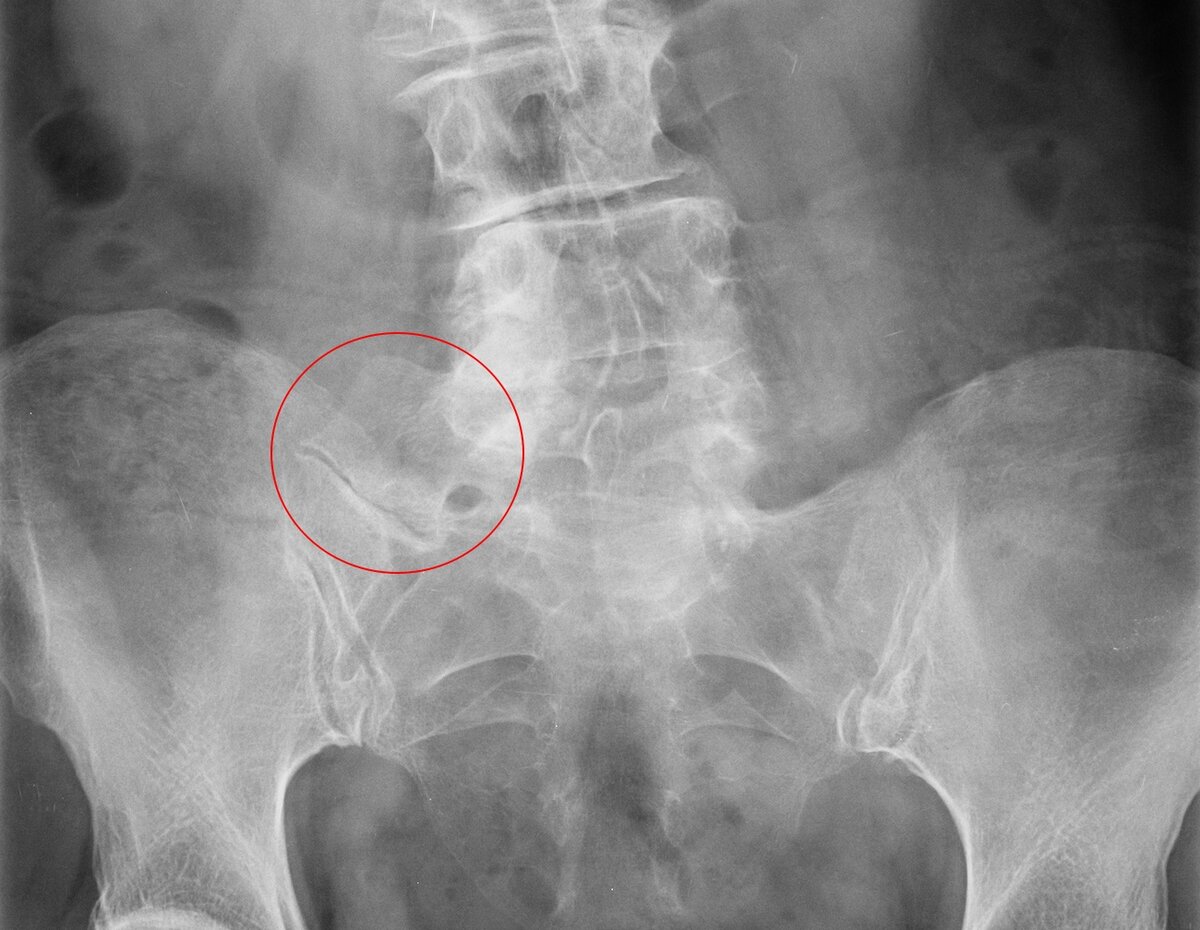

El síndrome de Bertolotti se origina por una variación genética en la región lumbosacra. De forma específica, la quinta vértebra lumbar (L5) presenta una fusión parcial o completa con el sacro o con el hueso de la pelvis (ilion).

Esta conexión anormal da lugar a una pseudoarticulación que modifica la biomecánica normal de la columna, aumentando la carga sobre los discos intervertebrales y los nervios cercanos, lo que favorece la aparición del dolor.

Uno de los principales retos es identificar correctamente esta condición. El diagnóstico se apoya en estudios de imagen como radiografías lumbosacras, tomografía computarizada y resonancia magnética. Además, las infiltraciones diagnósticas con anestésico local en la zona afectada pueden confirmar el origen del dolor si este desaparece tras el procedimiento.